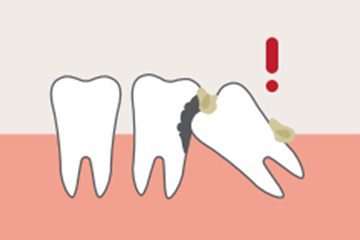

좁은 곳에 나기 때문에 누운 상태로 나거나, 턱뼈를 자극하는 각도로 뿌리를 내리거나, 잇몸에 숨겨진 상태로 나는 등 비정상적으로 자리를 잡게 되기 쉽습니다. 그리고 사랑니는 치열 안쪽 깊숙이 자리해 있기 때문에 칫솔질이 닿기 힘듭니다.

칫솔질이 잘 닿지 않는 사랑니와 옆 치간에는 음식물 등 세균이 잔류하게 됩니다. 잔류 음식물이나 세균 등은 결국 치태가 되고 치태는 치석이 되어 사랑니뿐만 아니라 사랑니 근처 치아에까지 충치와 치주 질환을 유발하게 됩니다.